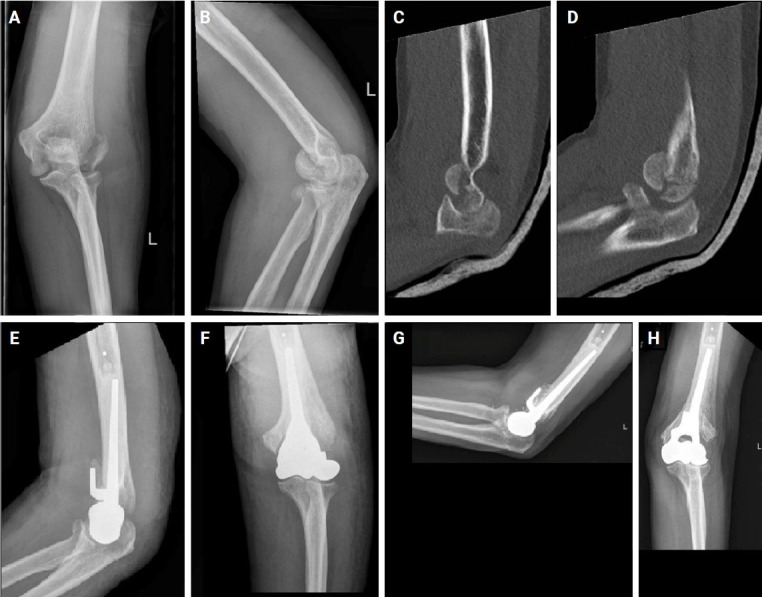

背景:评价肱骨远端半关节置换术(DHH)治疗8例肱骨远端骨折不可重建或切开复位内固定(ORIF)失败的患者的疗效。方法:回顾性资料包括人口统计学、术后结局和并发症,从一家一级创伤中心的电子记录中提取。手术由一名训练有素的上肢外科医生进行。DHH的适应症为肱骨远端不可重建骨折或ORIF失败。最终,正如当前文献所接受的那样,没有施加重量限制。在随访期间评估活动范围(ROM)、功能评分和疼痛水平。最小随访时间为12个月。结果:2014 - 2024年间,连续8例患者接受了DHH。手术时患者平均年龄为68.1岁,平均随访46.6个月。患者表现出满意的关节活动度,前旋接近完全,平均屈伸分别为125°和25°。功能评分,包括手臂、肩膀和手的快速残疾评分(35.2)和Mayo肘部表现评分(78.1),均良好。平均数值疼痛评定量表为3.9。并发症包括2例因肘关节不稳定和术后感染而进行全肘关节置换术(分期转换),1例因肘关节术后不稳定而进行韧带重建,2例尺假体周围骨折,1例尺神经病变。结论:对于无法重建的肱骨远端骨折和ORIF失败的DHH,允许无限制的术后抬起,并产生令人满意的功能结果,但确实有相对较高的并发症发生率。证据等级:四级。

Background: To evaluate the outcomes of distal humerus hemiarthroplasty (DHH) in a series of eight consecutive patients with unreconstructible distal humeral fractures or failed open reduction and internal fixation (ORIF).

Methods: Retrospective data including demographics, postoperative outcomes, and complications were extracted from electronic records at a level 1 trauma center. Surgeries were performed by a single fellowship-trained upper extremity surgeon. The indications for DHH were unreconstructible distal humerus fracture or failed ORIF. Eventually, as accepted by current literature, no weight restrictions were applied. Range of motion (ROM), functional scores, and pain levels were evaluated during follow-up appointments. Minimum follow-up time was 12 months.

Results: Between 2014 and 2024, eight consecutive patients underwent DHH. The mean patient age at the time of surgery was 68.1 years, with an average follow-up of 46.6 months. Patients exhibited satisfactory ROM, with near-complete pronosupination and mean flexion and extension of 125° and 25°, respectively. Functional scores, including Quick Disabilities of the Arm, Shoulder and Hand score (35.2) and Mayo Elbow Performance Score (78.1), were good. Mean Numeric Pain Rating Scale was 3.9. Complications included two conversions to total elbow arthroplasty due to elbow instability and postoperative infection (staged conversion), one ligament reconstruction for postoperative elbow instability, two cases of ulnar periprosthetic fracture, and one case of ulnar nerve neuropathy.

Conclusions: DHH for unreconstructible distal humerus fractures and failed ORIF allows for unrestricted postoperative lifting and yields satisfactory functional outcomes but does have a relatively high complication rate. Level of evidence: IV.